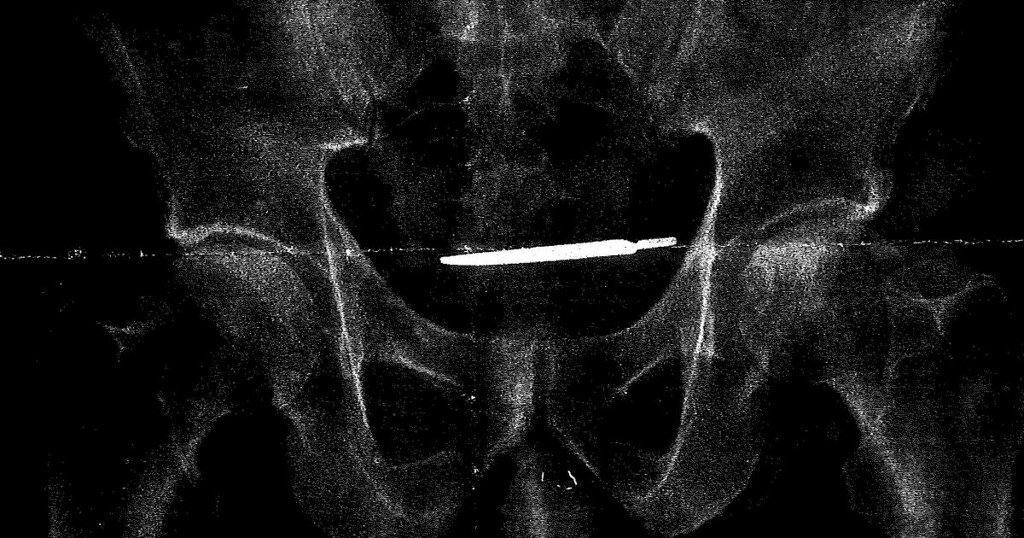

One single VA purchased scalpel cost taxpayers over $1000, and this patient received it for free.

It is a scalpel handle... no blade. A retained blade would have manifested itself FAR sooner. Not to diminish the fact that this is a sentinel event... it certainly is. But let’s be honest and accurate in reporting.